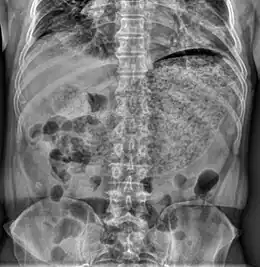

Description de l'image GastroparesisXray.jpg.